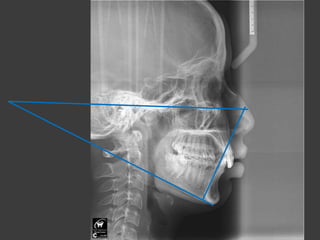

 The Tweed cephalometric triangle is constructed.

 This triangle is based upon the Frankfort horizontal

plane , the mandibular plane and the axis of the

mandibular incisor.

 FMPA is 20 – 29 degree ----- FMIA should be 68 degree.

 FMPA is 20 degree or less ----- IMPA is 91 degree.

 FMPA is 30 degree or more ----- FMIA should be 65

degree.

 If FMPA is low , the mandibular incisor should not be

pushed forward from their original position if the muscular

balance is normal.

 Therefore , extractions are often necessary if the anterior limit

of the dentition is to be respected in the presence of significant

anterior crowding and / or protrusion.

FMPAA

FMIA

IMPA

FHP

MP

Long axis

of the

lower

incisor